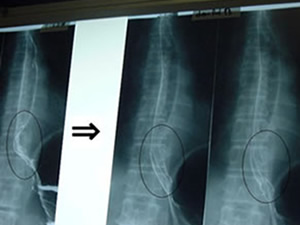

なんと、執刀を決定する1週間前に、

食道を塞いでいた6センチに膨れ上がった

悪性の腫瘍がスッポンと消滅してしまったのです(写真参照)。

専門的には「寛解」(かんかい)といいます。

6センチの腫瘍(左)が奇跡的に消滅(右)